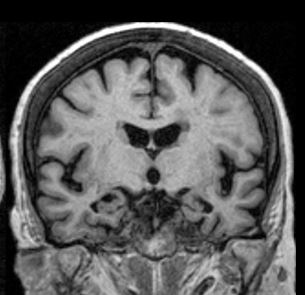

이 유전자를 갖고 있으면 그렇지 않은 사람보다 알츠하이머 치매에 걸릴 위험이 10배가량 높은 것으로 알려져 있으며 나이가 들면서 뇌 인지 기능이 점진적으로 떨어지는 알츠하이머 치매는 유전율(Heritability)이 높은 병 중 하나이다.

질병이 발병하는 여러 요인 중 유전적 요인이 기여하는 비율이 상대적으로 높다는 의미로 알츠하이머 치매와 관련된 대표적인 유전자는 ApoE(아포이·ApolipoproteinE)다. 부모로부터 각각 1개씩 물려받은 ApoE 유전자는 어떤 조합을 갖고 있느냐에 따라 알츠하이머 치매 발병 위험이 달라진다.

문제가 되는 것은 ApoE4 유전자가 포함된 유전형 조합이다. ApoE4는 뇌 속에 아밀로이드 베타, 타우 단백질 등이 더 많이 쌓이게 만들어 알츠하이머 치매 발병 위험을 높인다고 하며 ApE4 유전형을 하나만 물려받아도 알츠하이머 치매 발병 위험이 올라간다는 의미이기도 합니다.

고려대안암병원 신경과 이찬녕 교수는 “ApoE4가 하나만 있을 땐 알츠하이머 치매 위험이 3~4배, 부모 양쪽에서 ApoE4 유전자를 모두 받았다면 나이가 들어 치매에 걸릴 위험이 8~12배 높아진다”고 말했습니다.

전 세계적으로 5명 중 1명(20%)은 ApoE4 유전자를 한 개 갖고 있다고 밝혀졌으며 특히 한국인을 포함한 동아시아인은 ApoE4 유전자의 T타입 유전변이로 서양인보다 알츠하이머 치매에 더 취약하다고 알려져 있습니다.

한국인에게 더 치명적인 ApoE4 유전변이와 알츠하이머 치매의 연관성을 분석한 조선대 의생명과학과 이건호 교수는 “똑같은 ApoE4 유전자를 갖고 있어도 T타입 유전변이율이 90%로 높은 한국인은 서양인보다 뇌 손상 범위가 넓어 평균 2년 이상 빨리 알츠하이머 치매가 발병한다”고 말하기도 했습니다.